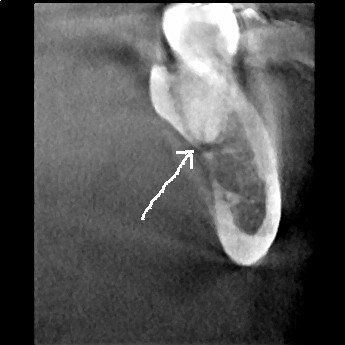

A sagittal slice through the distal root of #18 shows the lesion and its perforation of the lingual plate.

An axial view of the distal root of #18 also shows perforation to the lingual.

These CBCT slices are conclusive enough to revise the pulpal diagnosis to “partially necrotic” and recommend endodontic treatment. It appears that the distal root is necrotic and the infection is spreading through the lingual plate.